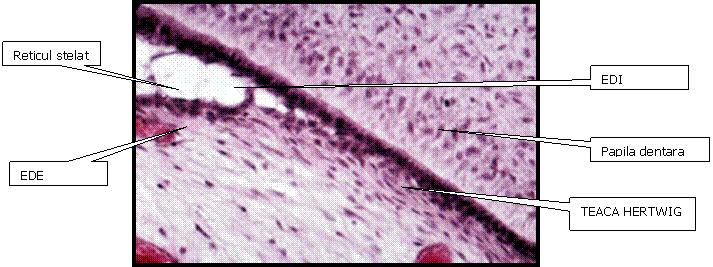

EDI se uneste cu Epiteliul Dentar Extern (EDE) rezultand Epiteliul Dentar Redus cu rol de protectie intraosoasa a coroanei fata de tesutul conjunctiv inconjurator, in caz de activitati terapeutice stomatologice, patologii intraosoase. Daca nu va proteja bine coroana pot aparea Hipoplazii, Hipomineralizari de smalt.

Teaca HERTWIG e responsabila de formarea radacinii. Ea are origine epiteliala si are ca roluri dirijarea formarii radacinii si inductia odontoblastelor pentru formarea dentinei radiculare.

Teaca Hertwig are 2 componente:

Diafragmul epitelial, in partea terminala a tecii, are o portiune relativ fixa.

Cand coroana a ajuns sa se formeze pana la jonctiunea smalt-cement, epiteliul de la bucla cervicala incepe sa prolifereze sub forma orizontala, inspre zona papilei dentare, aparand o separatie intre acea zona si sacul folicular. Acea zona va ramane fixa pe toata durata formarii radacinii.

La zona de cudura teaca Hertwig va prolifera avand efect inductor pe odontoblastele din papila dentara, care la randul lor vor produce o mica cantitate de dentina. Apoi teaca Hertwig va fi fragmentata de celulele nediferentiate in sacul folicular. Celulele nediferntiate vor deveni : cementoblasti ( depun cement), Osteoblasti (depun os) si Fibroblasti ( depun ligamntele alveolo-dentare).

Resturile tecii Hertwig = RESTURILE LUI MALASSEZ ( pot fi surse de chisturi)